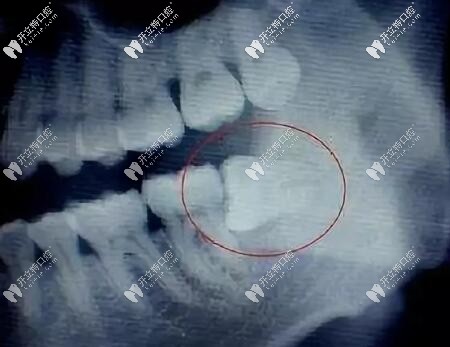

阻生智齒圖片

但有一些智齒,傾斜長(zhǎng)的,或者水平長(zhǎng)的,或者是埋在骨頭里的,有些還壓著神經(jīng)管的,這時(shí)候就需要將牙肉切開(kāi),去除周?chē)墓穷^。

阻生智齒

智齒牙片

尤其橫生智齒,一顆橫生的智齒,普通的鉗子是拔不出來(lái)的,需要拿出渦輪機(jī)磨開(kāi),醫(yī)生還要判斷感染的風(fēng)險(xiǎn)等等,所以這些背后體現(xiàn)的是醫(yī)生的經(jīng)驗(yàn)。